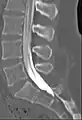

Myelogram showing arachnoiditis in the lumbar spine.